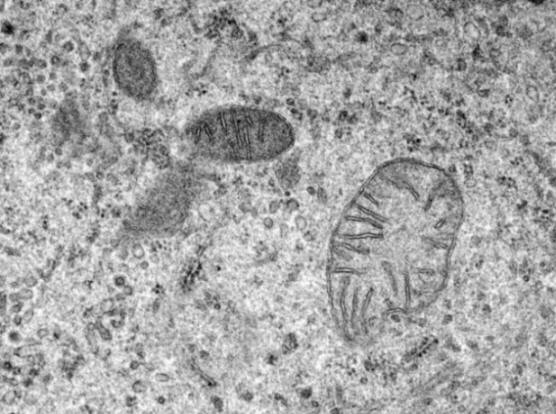

8. Kako rade mitohondrije?

Fotografija iz otvorenih izvora

Mitohondrije su sastavni dio našeg tijela. Jedina svrha mikroskopskih organela je transformirati sve hrana koju konzumiramo za energiju. Dugo vremena nismo znali mitohondrije gotovo ništa, ali nauka je blizu razumijevanja kako rade.

U novije vreme naučnici su saznali kako mitohondriji nose energiju. Naučnici su takođe saznali da mitohondrije zaista vole kalcijum, što ponekad može uzrokovati probleme: ako se mitohondriji apsorbiraju previše kalcijuma, može ubiti ćelije. To je zbog bolesti poput dijabetesa tipa 2.

Istraživači vjeruju da te bolesti utječu proces prenosa signala kroz koje tijelo komunicira mitohondrije, koliko se apsorbuje kalcijum i koliko se izlučuje. Nedavno je uspio da privede istraživački tim sa Harvarda katalogizirati svaki protein u mitohondrijima, uključujući sve proteine, povezana s apsorpcijom kalcijuma. Za sada je malo informacija, ali ovo mi ćemo riješiti misteriju.